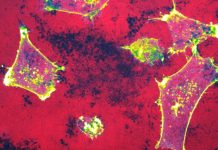

Non-coding RNAs (ncRNAs), in particular microRNAs (miRNAs), are emerging as critical regulators of cell fate and oncogenesis. miRNAs are a class of endogenous double-stranded RNAs 19-22 nucleotides long that repress activity of complementary messenger RNAs (mRNAs) selectively by targeting mRNA for degradation usually via complementary 3’-UTR seed sequences.

Cutting-edge advances in nanocarrier technology now allows us to accommodate payloads consisting of multiple ncRNA types that can be optimised for delivery to specific cell types, providing a high level of control to minimise off-target effects. We show that nano-carriers can be used to effectively deliver miRNA mimics and/or inhibitors (i.e. antagomirs) to regulate the GBM stem cell phenotype in vivo and this technology can be combined with other treatment modalities (e.g. radiation) to create a window of opportunity that sensitises tumour cells to chemo/radiation for long-term disease management7,8.

Our work with miRNAs highlights that understanding these context-specific, multi-dimensional interactions can lead to a sophisticated, mechanism-based, rational approach to designing molecular cancer therapeutics.